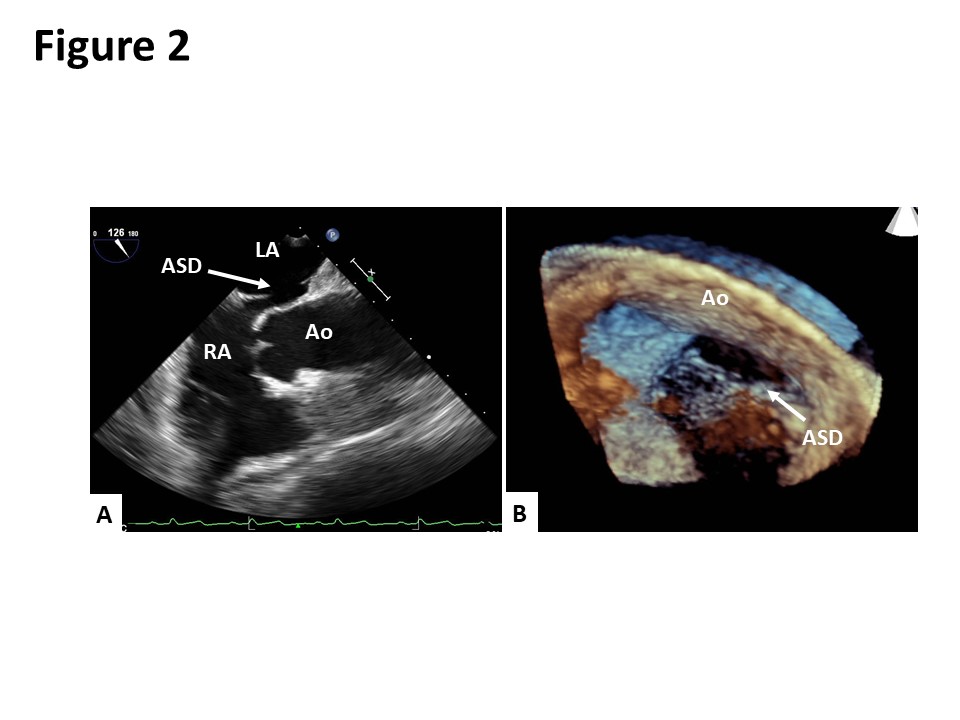

Case Presentation: An 80-year-old Japanese woman presented to our hospital with dyspnea in the sitting and standing positions. Two months prior to her admission, she had presented to another hospital with multiple vertebral compression fractures. After being discharged from the hospital, she developed dyspnea in the sitting and standing positions. She also reported an episode of syncope. Although the patient’s oxygen saturation on room air was 98% in the supine position, it declined to 83% in the sitting position and dropped further to 65% in the standing position. Contrast-enhanced computed tomography revealed the elongation of the aorta, which was compressing the right atrium and distorting the position of her heart (Figure 1). A transesophageal echocardiogram showed an oval-shaped secundum atrial septal defect (ASD) measuring 14 mm x 7 mm in size with a deficient aortic rim (Figure 2). The surgical closure of the ASD was performed. Following surgery, her oxygen saturation in the sitting and standing positions recovered to 98% on room air. She was discharged on the 23rd day after the surgery without any complaints of platypnea.

Discussion: Platypnea-orthodeoxia syndrome (POS) is a rare syndrome characterized by dyspnea and hypoxia when a patient is sitting or standing. The most common anatomical cause of POS is a right-to-left (RL) shunt through interatrial communications, including an atrial septal defect (ASD) or patent foramen ovale (PFO). In our case, based on the patient’s clinical course, her multiple vertebral compression fractures were suspected to have triggered the exacerbation of the RL shunting. To the best of our knowledge, only three cases of POS induced by vertebral fractures have been reported. A possible etiological mechanism to explain the induction of POS by vertebral fractures is as follows: the multiple vertebral compression fractures caused kyphosis and the subsequent distortion of the aorta resulting in right atrial compression and increased RL flow through the ASD.